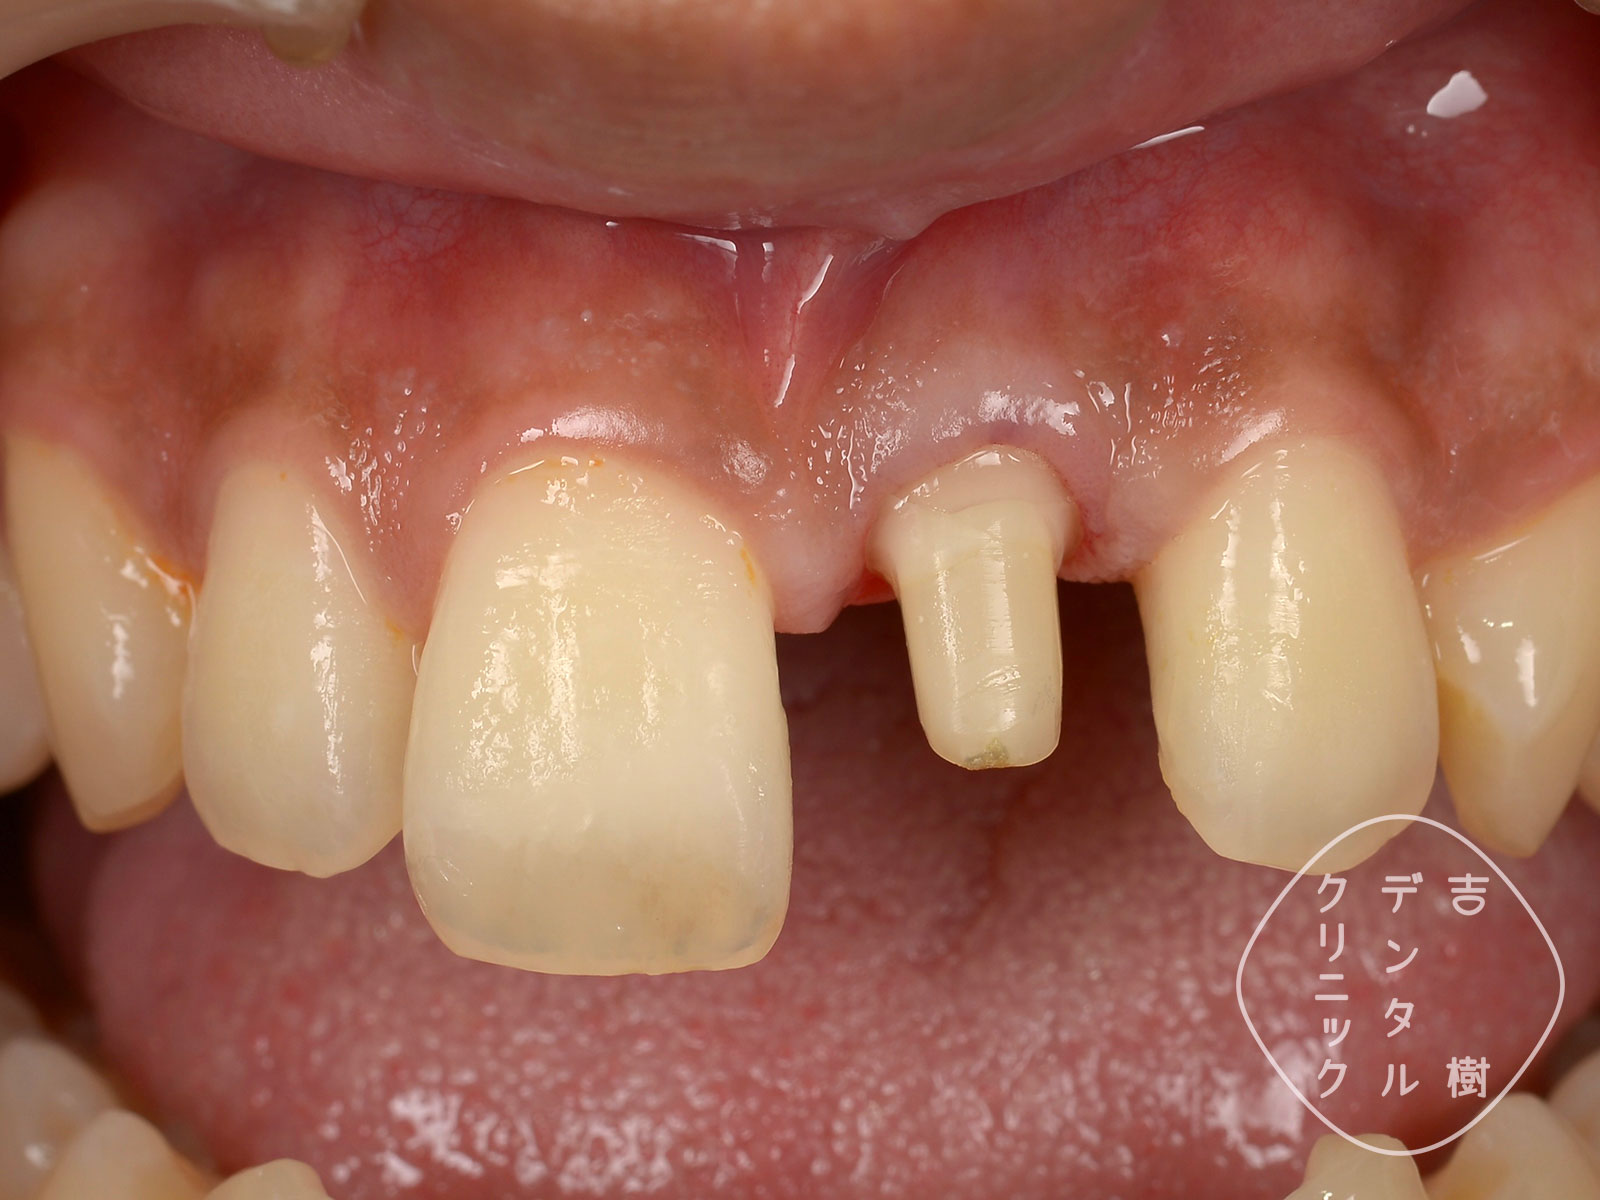

歯を強くぶつけてしまったなどに、歯が折れてしまうことがあります。歯茎から外に出ている白い部分が折れてしまうことを、「歯冠破折(しかんはせつ)」といいます。

歯冠破折が起こったら、なるべく早めの受診をお勧めします。折れたところは鋭くとがっていることがあるので、唇や舌などを傷つけてしまうことがあります。また、折れたところは虫歯になりやすいので、早めに処置した方が予後が良くなります。

当院では、「ダイレクトボンディング」という治療法で、歯冠破折を修復できます。歯が折れた当日に修復することも可能です。

破折の当日にダイレクトボンディングで修復したケース。